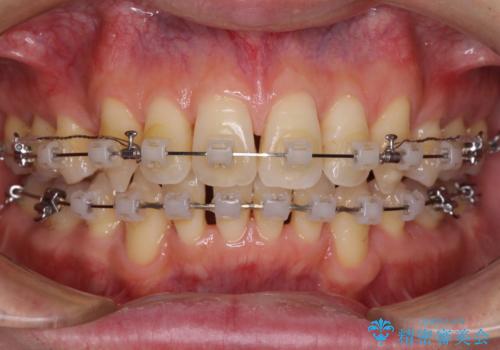

- クリアブラケット

- 2年

今回の治療では、奥歯が前方に傾斜した歯並びだったため、奥に起き上がることで歯列が後方に移動し、横側からも口元が引っ込んだ感じが分かるほど改善されました。